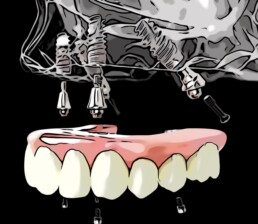

Wieder eine Woche vergangen. Heute erklären wir, wie All-on-4 mit 4 Zahnimplantaten eigentlich genau funktioniert. An einem Tag werden die restlichen schlechten Zähne entfernt, sofort die 4 Implantate gesetzt und nach einer notwendigen Abformung (das geht mit unserem vorhandenen modernem Scanner aus technischen Gründen leider nicht gleich nach der Operation), wird nach spätestens 24 Stunden der neue Zahnersatz als festsitzende Brücke auf die Implantate geschraubt. Man lernt eine Prothese niemals kennen, das ist das, was viele Patient:innen einfach wollen. Bei fragen bitte einfach per email über die Homepage.

Der Implantat-Quickie geht in eine neue Runde. Ab heute geht nun jeden Dienstag ein neues Video online, welches sich mit All-on-4 beschäftigt. Zu diesem Thema haben nämlich viele Patient:innen einige Fragen, die wir alle gerne kurz und knackig beantworten wollen. Feste Zähne an nur einem Tag, Neues Lächeln über Nacht- und das mit nur 4 speziellen Zahnimplantaten in Krems. Solltet ihr Fragen zu All-on-4 oder zu implantaten haben, dann bitte einfach per email über die Homepage. Und nun zum ersten Video. Viel Spaß damit.